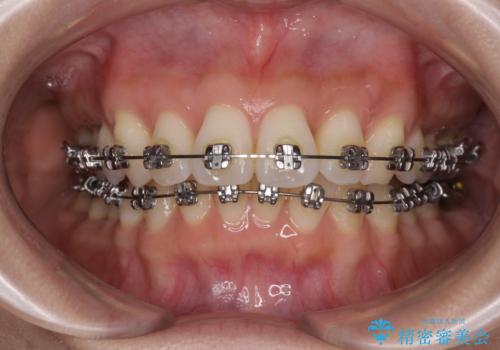

上顎前突をしっかりと治す 補助装置を使用したワイヤー矯正

奥歯の噛み合わせをみると、上顎歯列が全体的に前突している状態であり、この咬み合わせのまま歯列を整えると出っ歯になってしまう可能性がありました。

アンカースクリューと補助装置を使用して上顎大臼歯を遠心移動させることで咬み合わせを改善し、ワイヤー装置によりデコボコを解消しながら口元の突出感も改善していくこととしました。

出っ歯になることなく、上下前歯が綺麗に接触する状態で仕上げることができました。